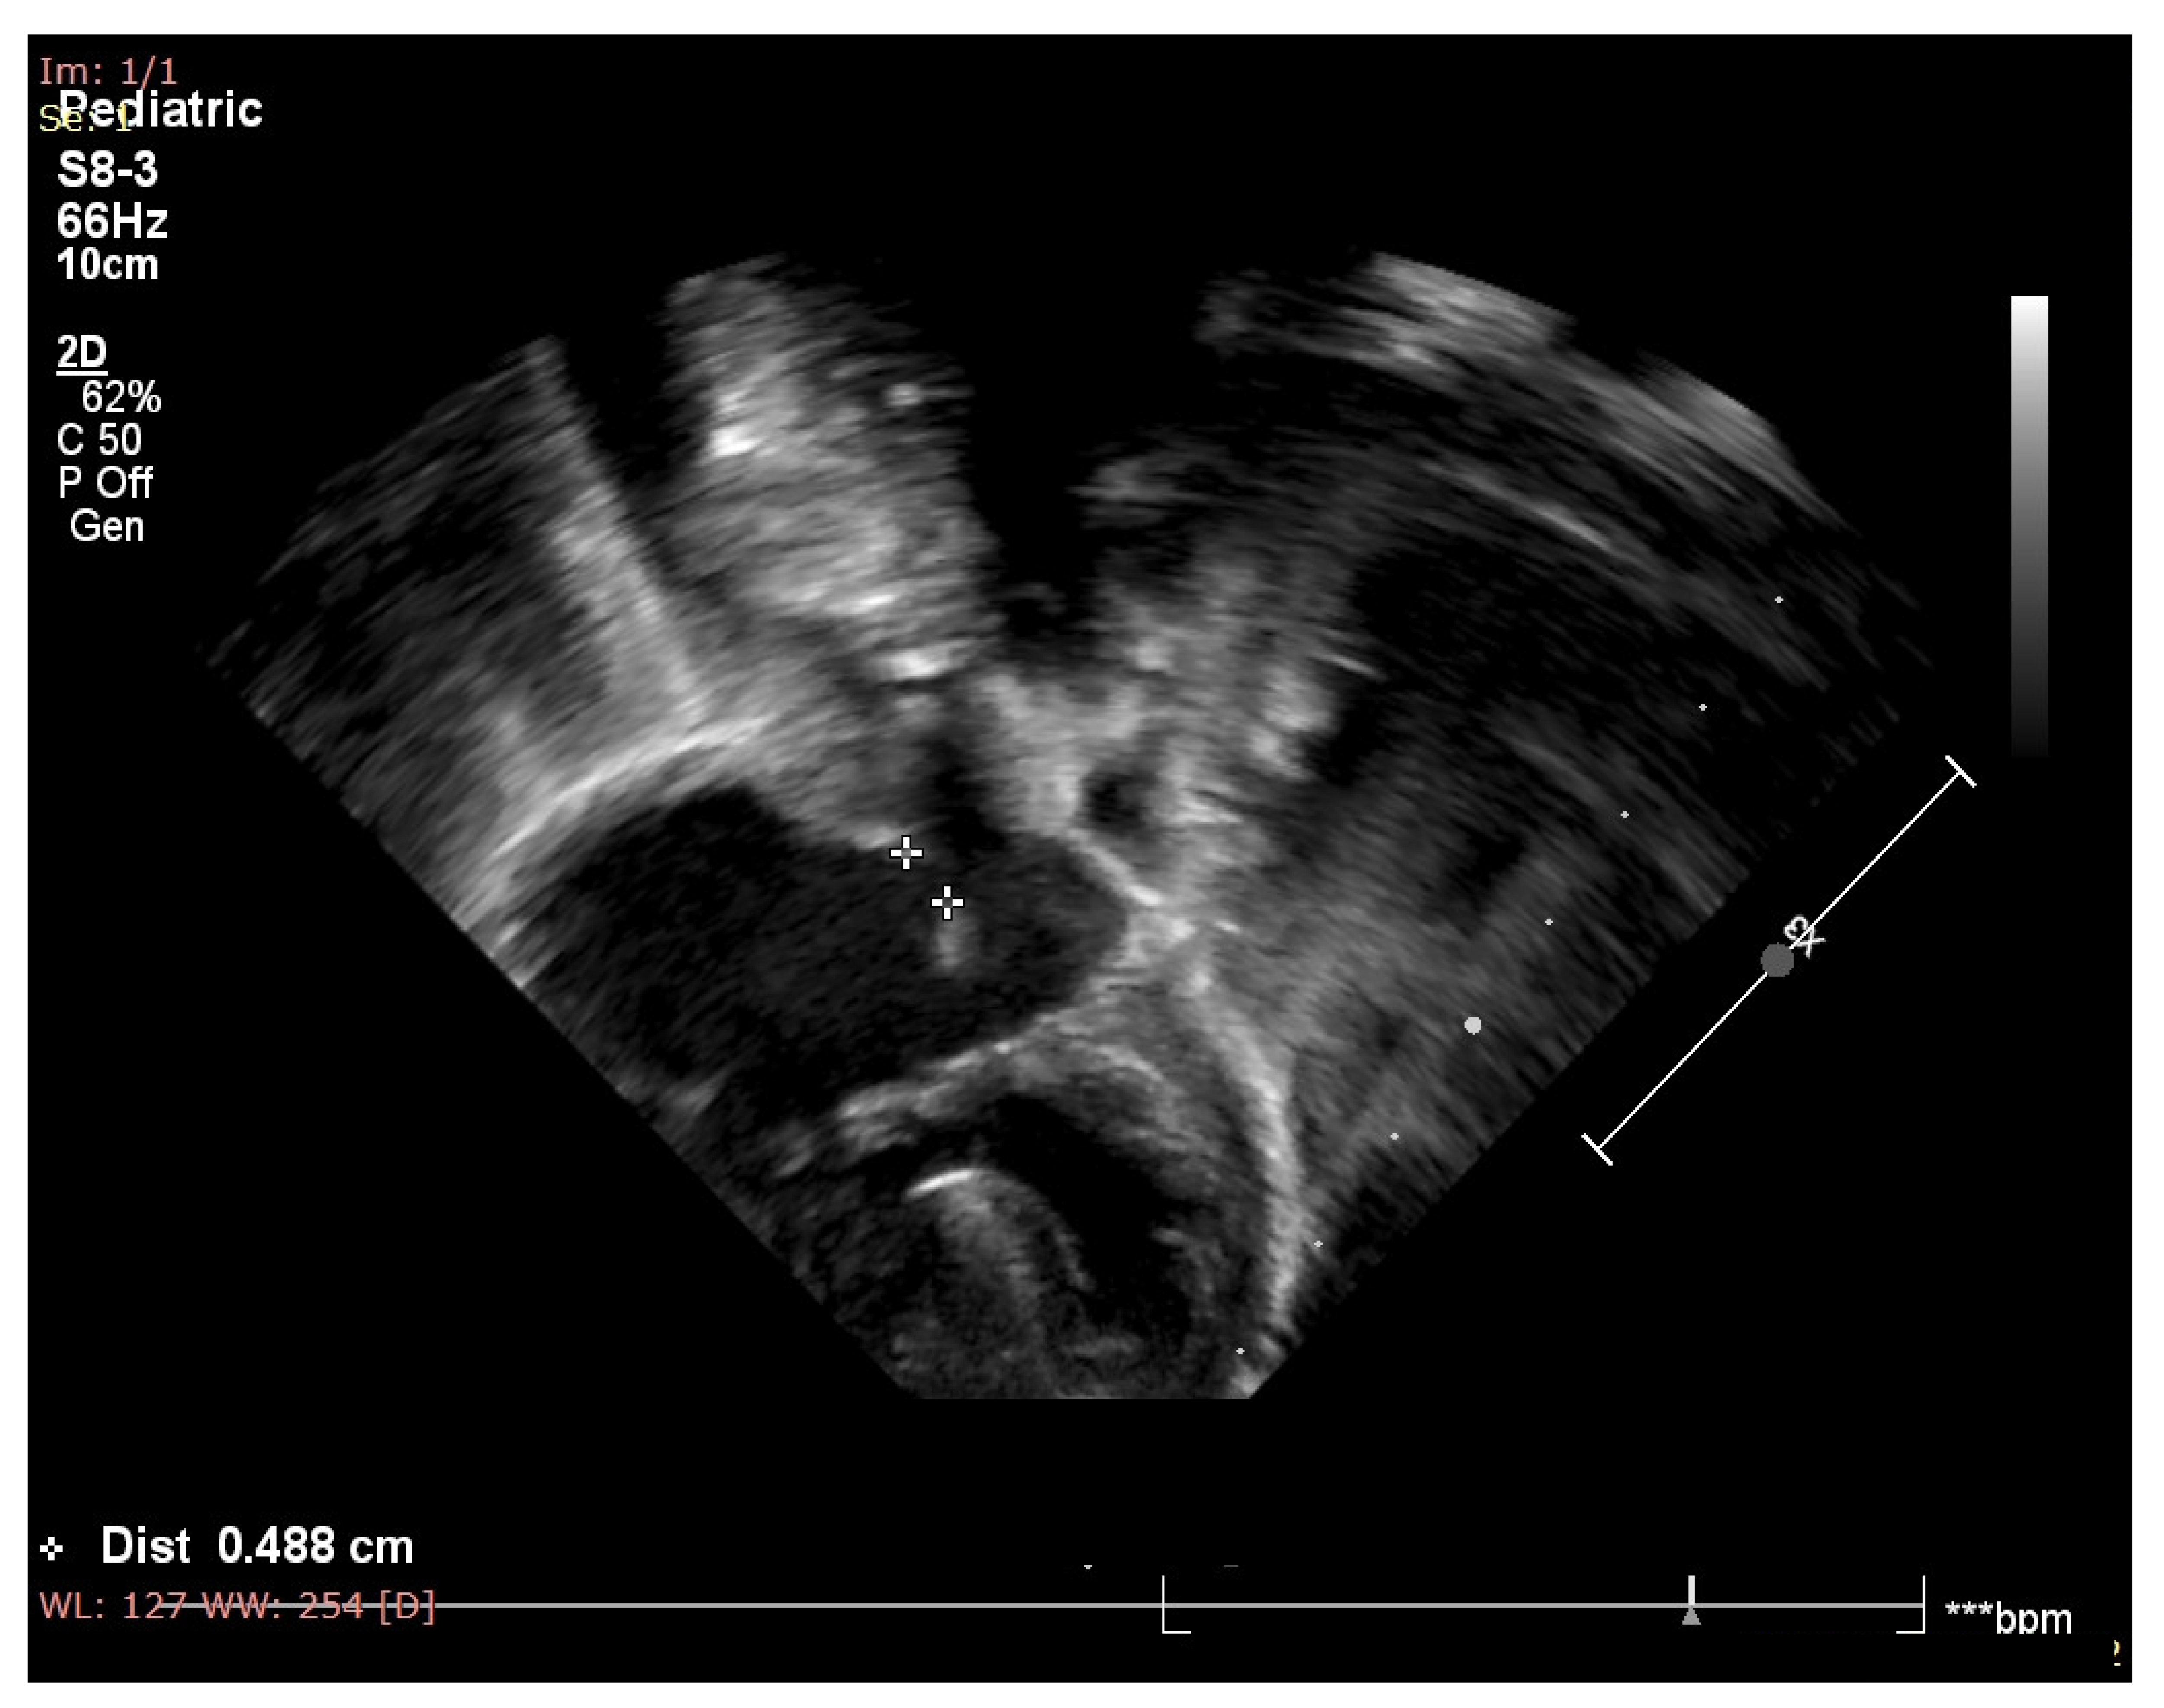

2. Case Report